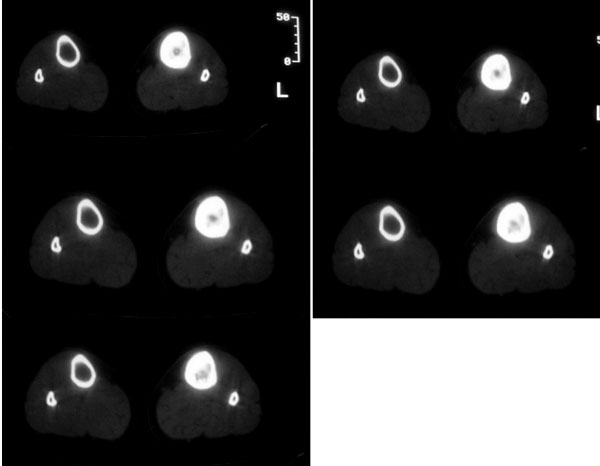

以下是引用卜一在2007-11-12 5:56:00的发言:[br]胫骨中上段骨内外膜增生,骨质硬化,部分骨皮质增厚,髓腔高度变窄,界限不清。多考虑:1 慢性低毒性感染。2 不除外骨纤维异常增殖症!